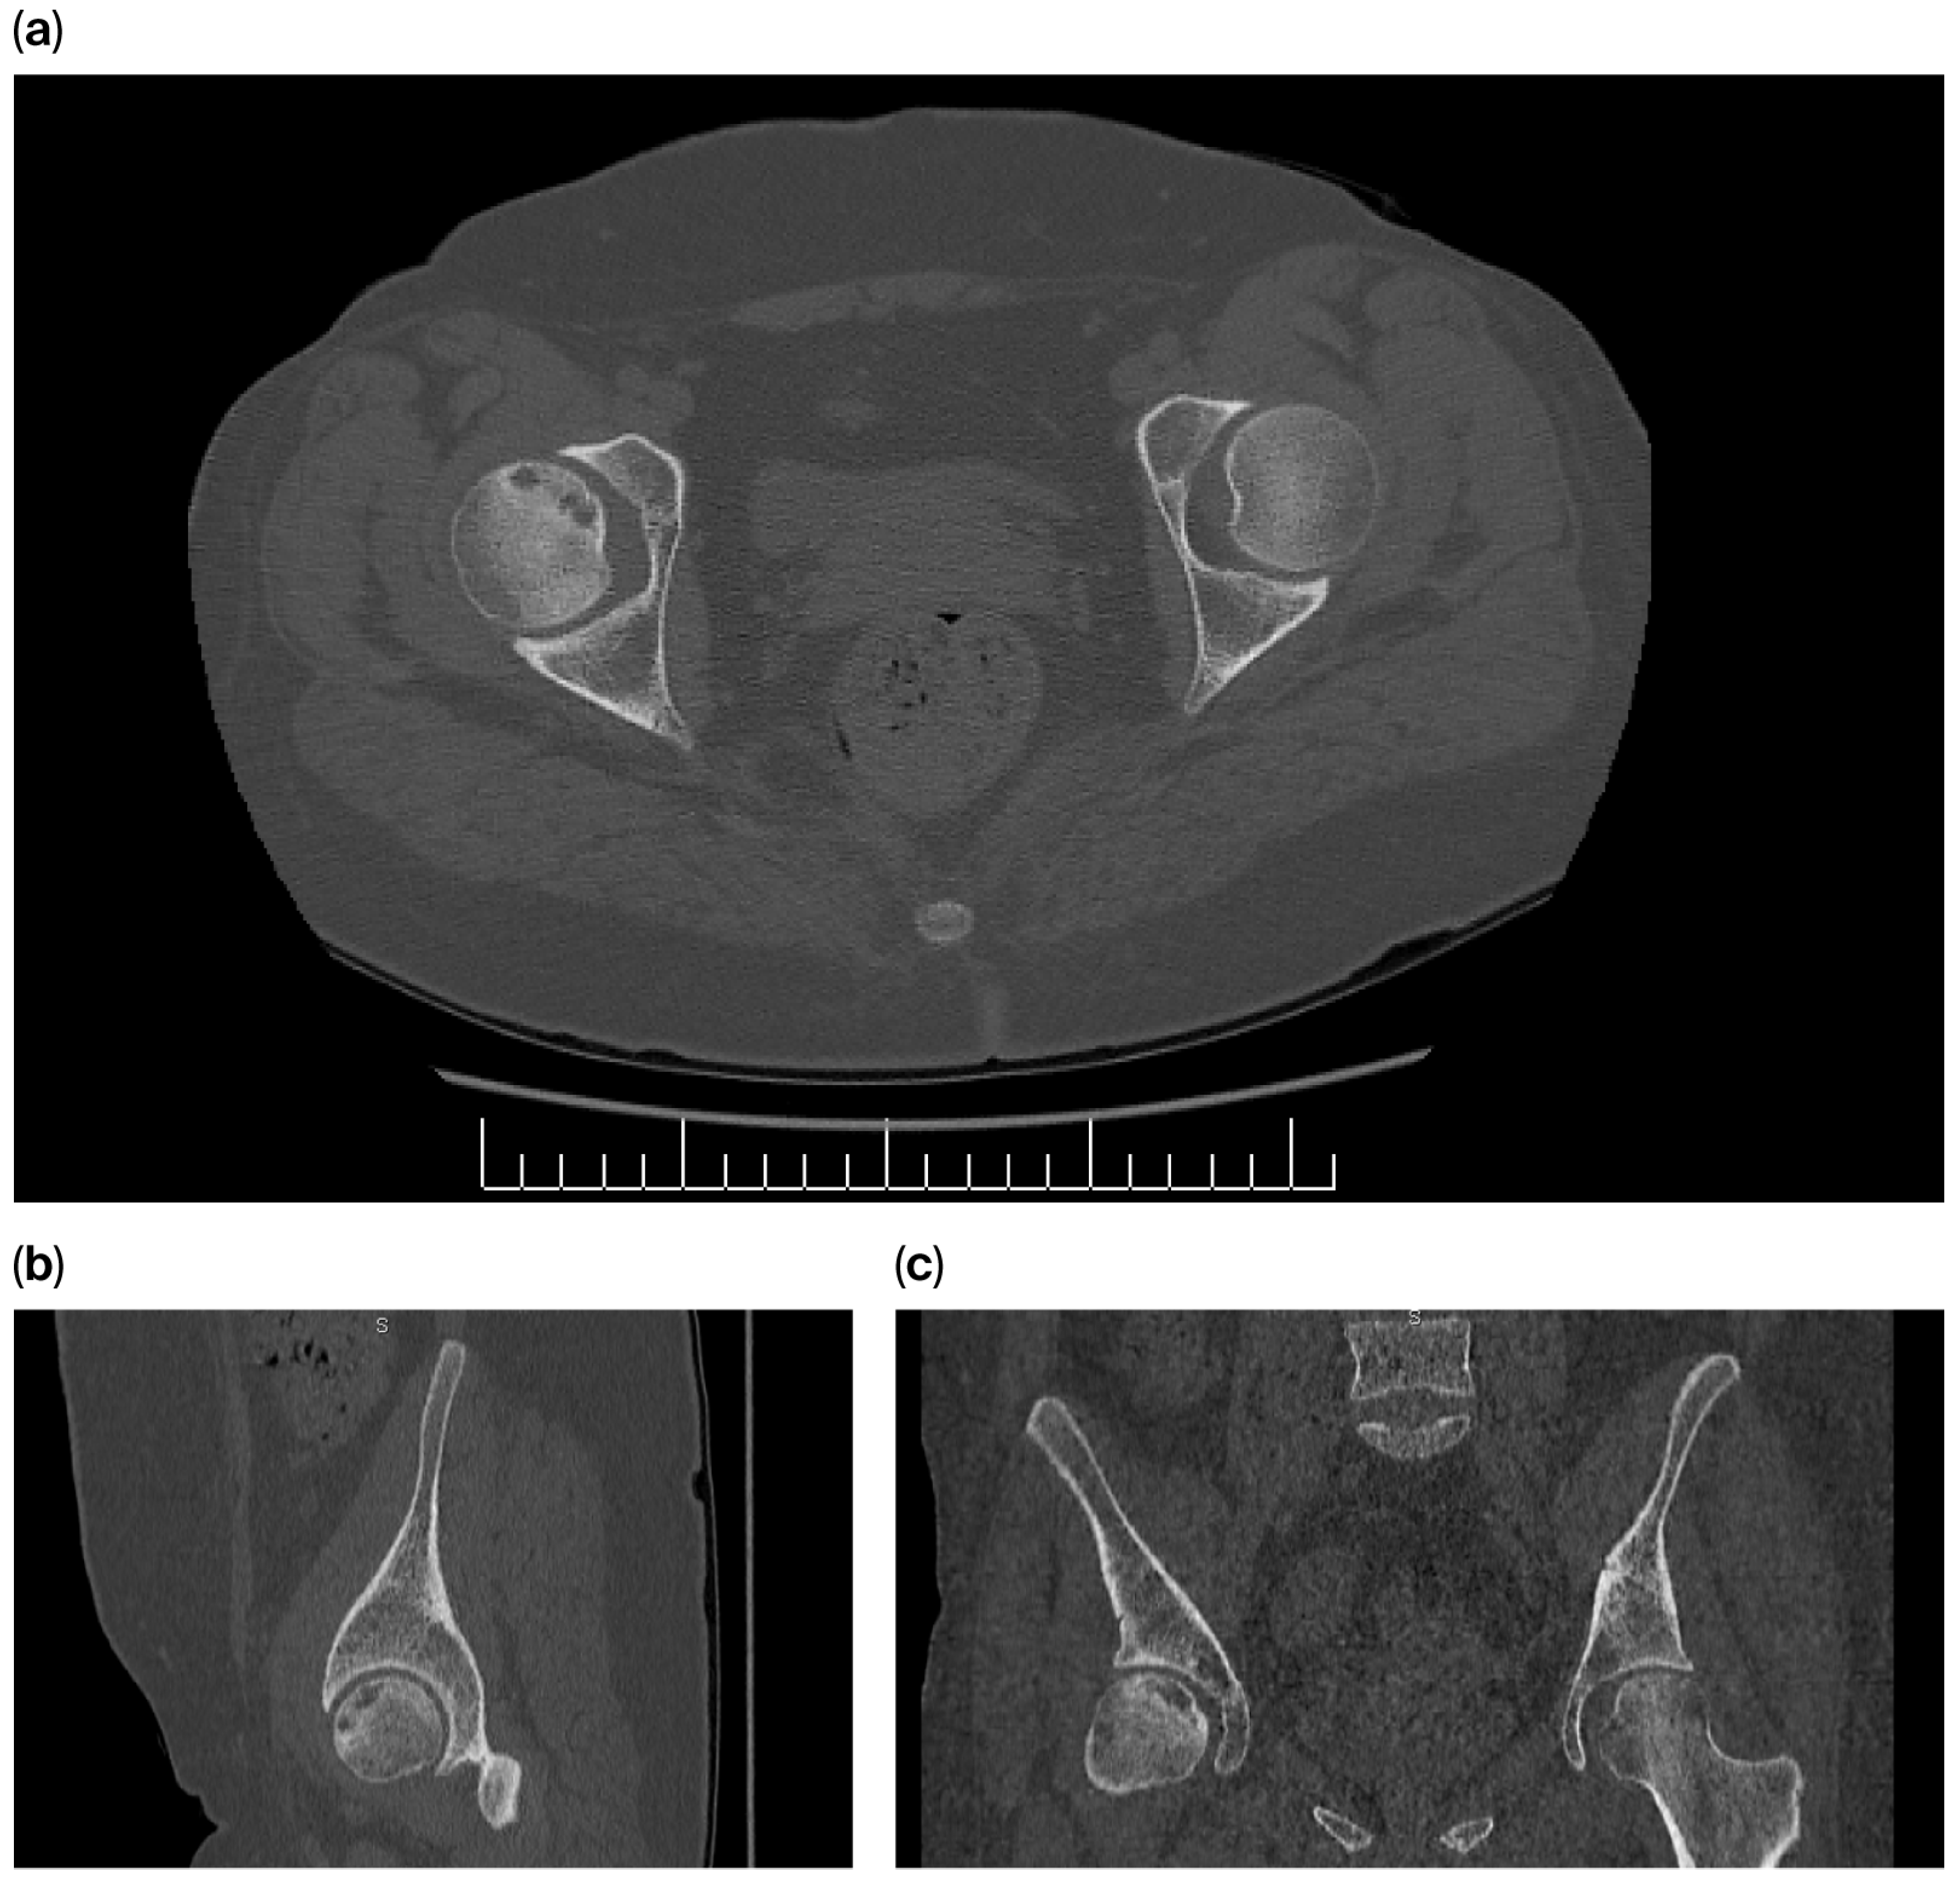

In May 2015, the patient presented with right inguinal pain; however, inguinal hernia was clinically ruled out. The presence of metallic sternal sutures precluded the magnetic resonance imaging (MRI) required to investigate a clinical suspicion of avascular necrosis (AVN) of the femoral head. The patient was considered at high risk for AVN due to multifactorial predispositions, including obesity, prolonged corticosteroid therapy, and a history of hematopoietic stem cell transplantation.

Pelvic CT imaging revealed Stage III osteonecrotic changes in the right femoral head. The findings included areas of osteosclerosis and confluent lesions bordering a subchondral radiolucent cystic area. A focal breach in cortical continuity with a subsequent minor indentation was observed, consistent with Stage III AVN. No pathological changes were noted in the right acetabulum or the contralateral hip joint (Figure 7).

Surgical intervention was deferred. The patient initiated a conservative management regimen consisting of swimming and a controlled weight-loss program, achieving a total reduction of 20 kg. These interventions resulted in significant alleviation of the coxofemoral pain, which subsequently resolved. Follow-up indicated bone remodeling with preservation of the femoral head architecture, thereby precluding the need for total hip arthroplasty.